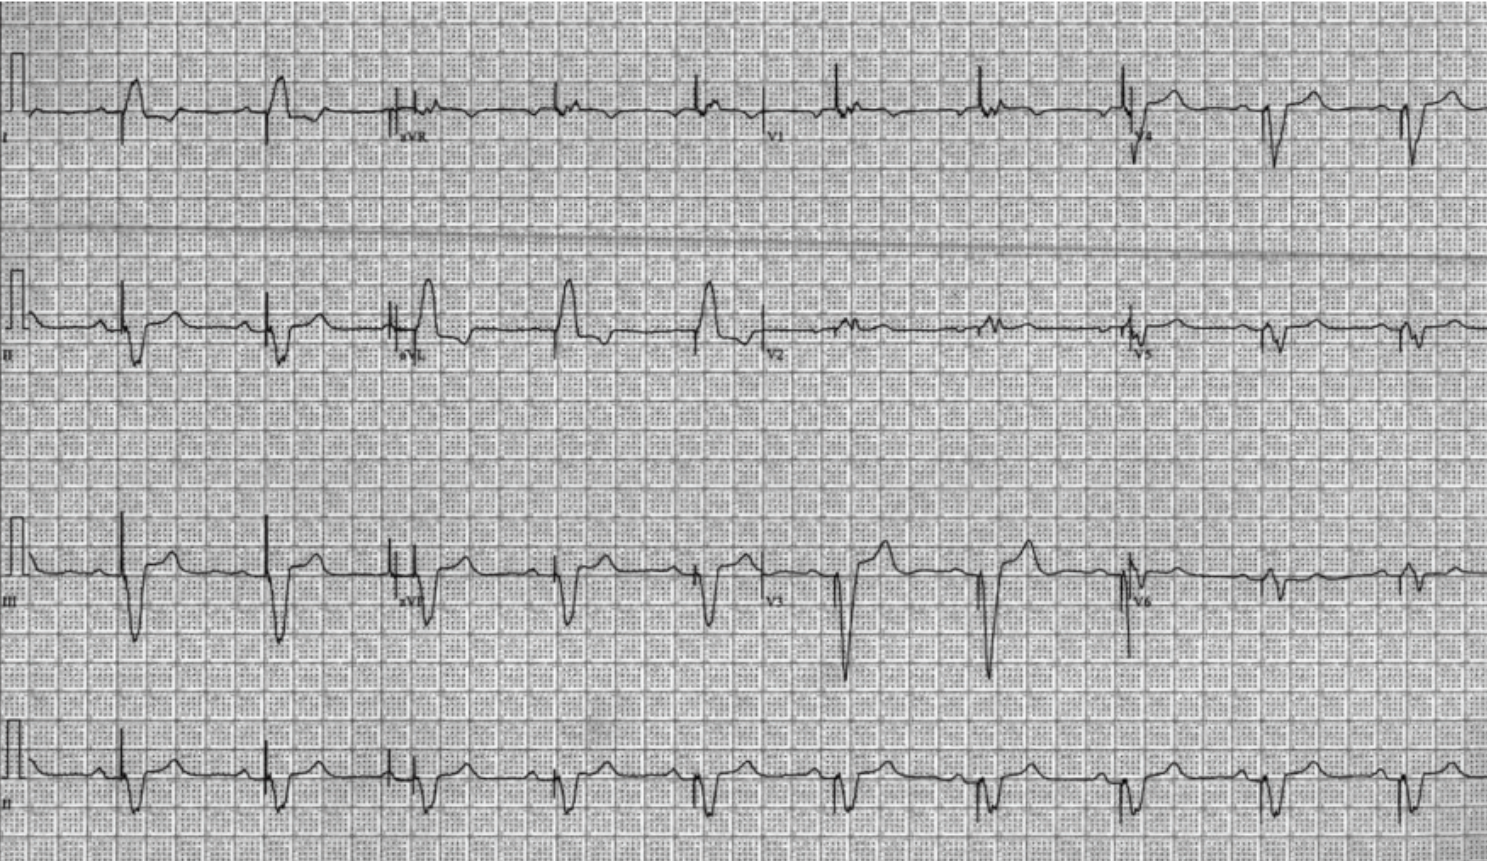

She was referred for consideration of extraction and reimplantation vs leadless pacemaker. Twelve-lead electrocardiogram (ECG) demonstrated a

ventricular paced rhythm at 61 beats per minute (bpm) (Figure 1). Device interrogation revealed increased RV lead noise, noise reversion, and inhibition resulting in inappropriate failure to output. Atrial parameters were unremarkable. Ventricular parameters were significant for an elevated capture threshold of 1.75 V at 0.4 ms, and labile impedances were consistent with impending fracture. We believe the recurrent fractures were due to the right-sided nature of the implant, tortuous vasculature, and the patient’s active lifestyle.